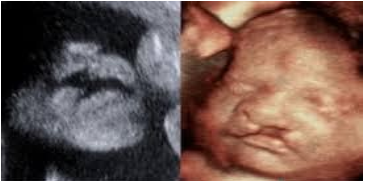

7. Có nên thực hiện xét nghiệm sàng lọc dị tật bẩm sinh không?

Có, xét nghiệm sàng lọc trước sinh đánh giá nguy cơ thai nhi có khuyết tật hoặc rối loạn di truyền. Xét nghiệm chẩn đoán trước sinh có thể phát hiện khuyết tật hoặc rối loạn di truyền. Quyết định nên được thảo luận với bác sĩ phụ sản hoặc chuyên gia y tế.